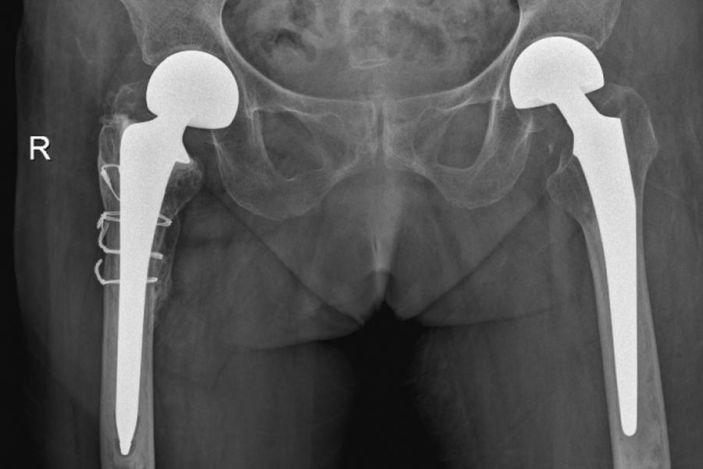

10月20日,老人家被送進了手術室行左側人工股骨頭置換術。吳主任根據方案按部就班地實施手術,娴熟地完成每一個手術步驟,精心地把控每一個細節,确保髋部良好的活動性和穩定性,以及雙下肢等長。整個手術過程非常流暢、一氣呵成。術中患者各項生命體征平穩,術後平安返回病房。

△右側(R)是賴婆婆3年前跌斷股骨術後,左側是本次手術術後。